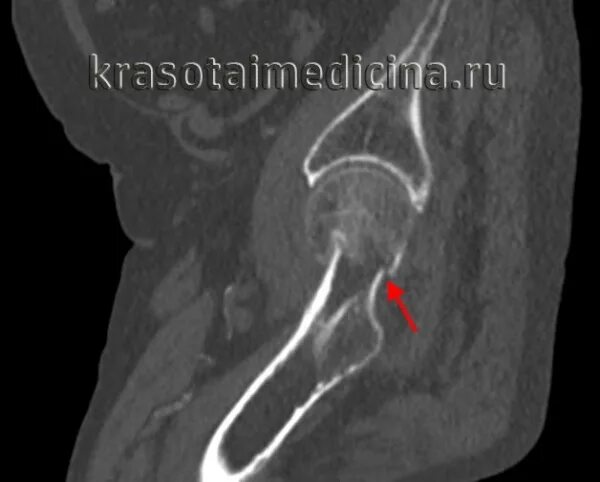

Перелом шейки бедра мкб 10 у взрослых